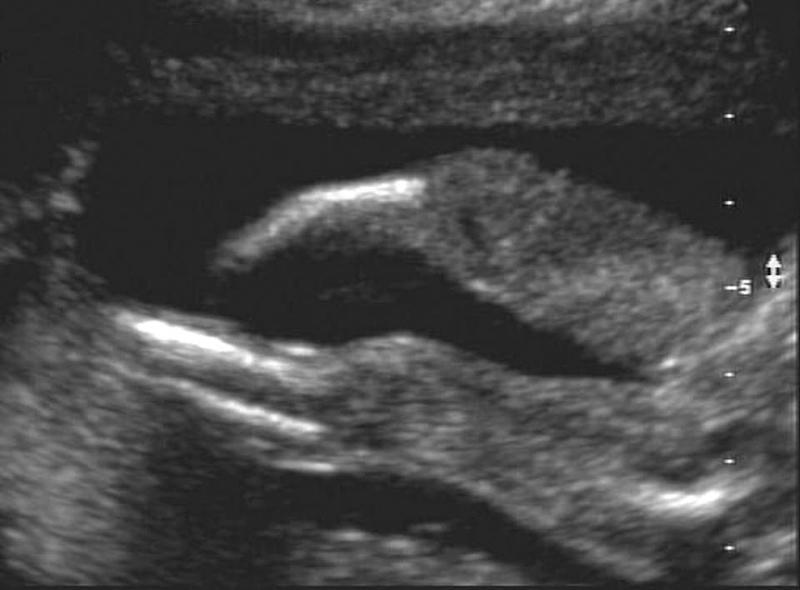

Hemimelia

What is Hemimelia?

Absence of below elbow or knee